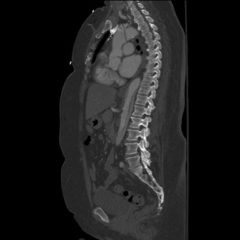

The anteroposterior X-ray reveals the classic steeple sign (blue outline) indicative of subglottic edema leading to tracheal narrowing, consistent with croup. The lateral x-ray shows narrowing of the subglottic region (green outline and arrows).

Laryngotracheobronchitis, croup, is a common respiratory infection causing inflammation of the larynx and trachea and affects 3% of children six months to three years of age.1 This swelling leads to the hallmark barking cough and inspiratory stridor frequently heard in young children with croup.2 While croup is a clinical diagnosis, radiographs are helpful and can assist in excluding other causes. The classic steeple sign associated with croup represents subglottic edema; it can be seen in other upper airway inflammatory conditions, and has been shown to be present in only 50% of croup cases, reinforcing that clinical acumen is very important in making this diagnosis.3